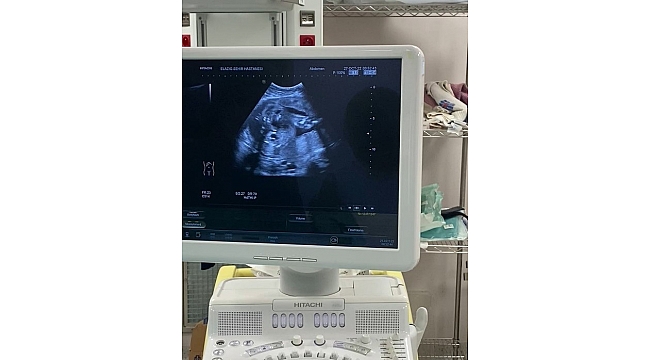

Fethi Sekin Şehir Hastanesi Perinatoloji Polikliniğine müracaat eden gebenin bebeğinde idrar yolu darlığı tespit edildi. Perinatoloji uzmanı tarafından yapılan detaylı muayene ve tetkiklerden sonra anne, bebek sağlığı için bebeğe stent takılması gerektiği belirlendi. Ultrason eşliğinde Vesicoamniyotik Stent takılan bebeğin idrarını yapması sağlandı.

Uygulanan işlemin oldukça hassas olduğunu ifade eden Perinatoloji Uzmanı Dr. Birsen Konukçu Palta, "Vesicoamniyotik Stent uygulması ile bebeğin idrar kesesine takılan bir kanül ile idrarını yapması sağlanır. Bu işlemin amacı bebeğin anne karnında içinde bulunduğu suyun devamlılığını sağlamaktır. Bize başvuran gebemizin bebeğinde idrar yolu darlığı tespit ettik. Öncelikle amniyosentez işlemi ile bebeğin genetiğinin normal olduğunu ve yaptığımız tetkiklerde böbreklerinin hala çalışır vaziyette olduğu belirledik. Şant yapılmasına karar verdiğimiz hastamıza sınırlı bir uyuşturma altında işlemimizi uyguladık. Ultrason eşliğinde yapılan işlem sonucunda bebeğimizin idrarını yapmasını sağladık" dedi.